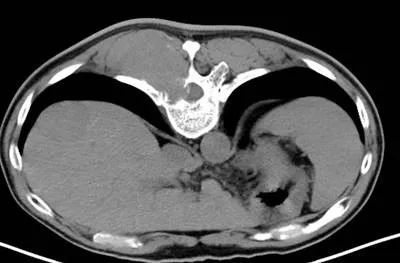

骨转移ct

肺癌骨转移ct图片